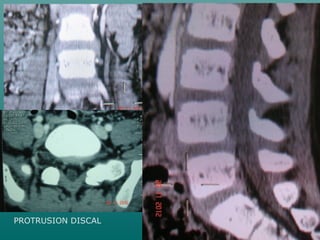

TEM DE COLUMNATEM DE COLUMNA

VERTEBRALVERTEBRAL

Protocolo para columnaProtocolo para columna

 INDICACIONES:INDICACIONES:

 MODO ESPIRAL PARA ESTUDIOS DEMODO ESPIRAL PARA ESTUDIOS DE

COLUMNA V.G. CAMBIOS POSTCOLUMNA V.G. CAMBIOS POST

TRAUMATICOS, TUMORES,TRAUMATICOS, TUMORES,

MALFORMACIONES O INDICACIONESMALFORMACIONES O INDICACIONES

ORTOPEDICA, ETC.ORTOPEDICA, ETC.

 UNA DISTANCIA DE 15 CM. SEUNA DISTANCIA DE 15 CM. SE

CUBRIRA EN 14.5 SEGUNDOSCUBRIRA EN 14.5 SEGUNDOS

PROTRUSION DISCAL

ESPINA BIFIDA OCULTA??